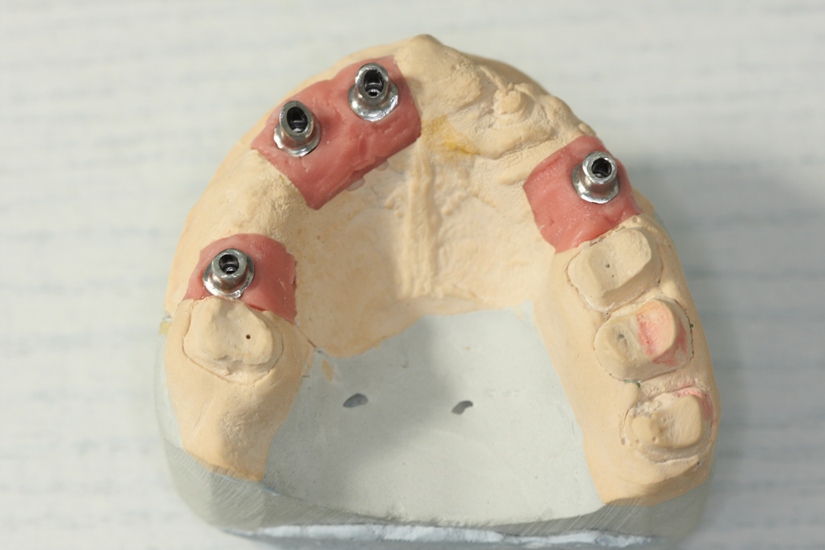

A temporary removable dental prosthesis was made at the stage of preparation

for the operation (Photo 3).

This was done in order to eliminate gingival reduction around the implants as well as to determine the real height of bite, horizontal line of cutting edge, location of central incisor midline and their compliance with the implants. Then the metal-ceramic bridge prostheses were made (Photo 14).